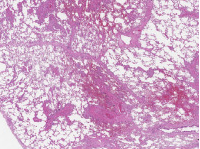

α) Νεκρωτική αγγειίτιδα. Διατοίχωμα φλεγμονή του αγγειακού τοιχώματος, με ή χωρίς ινοειδή νέκρωση. β) Νεκρωτική αγγειίτιδα μεσεντερικής αρτηρίας, με παναρτηριακή νέκρωση και παρουσία ινοειδούς νέκρωσης αγγειακού τοιχώματος. Ευγενική παραχώρηση Dr. V. Penopoulos.